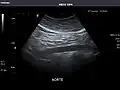

Abdominal Ultrasound (Full Exam)

STRUCTURED REPORT

(Technique: Transabdominal ultrasonography; Device: Toshiba Aplio XG)

Aorta: Visualized portions normal in caliber, 16 x 15 mm.

Aorta -